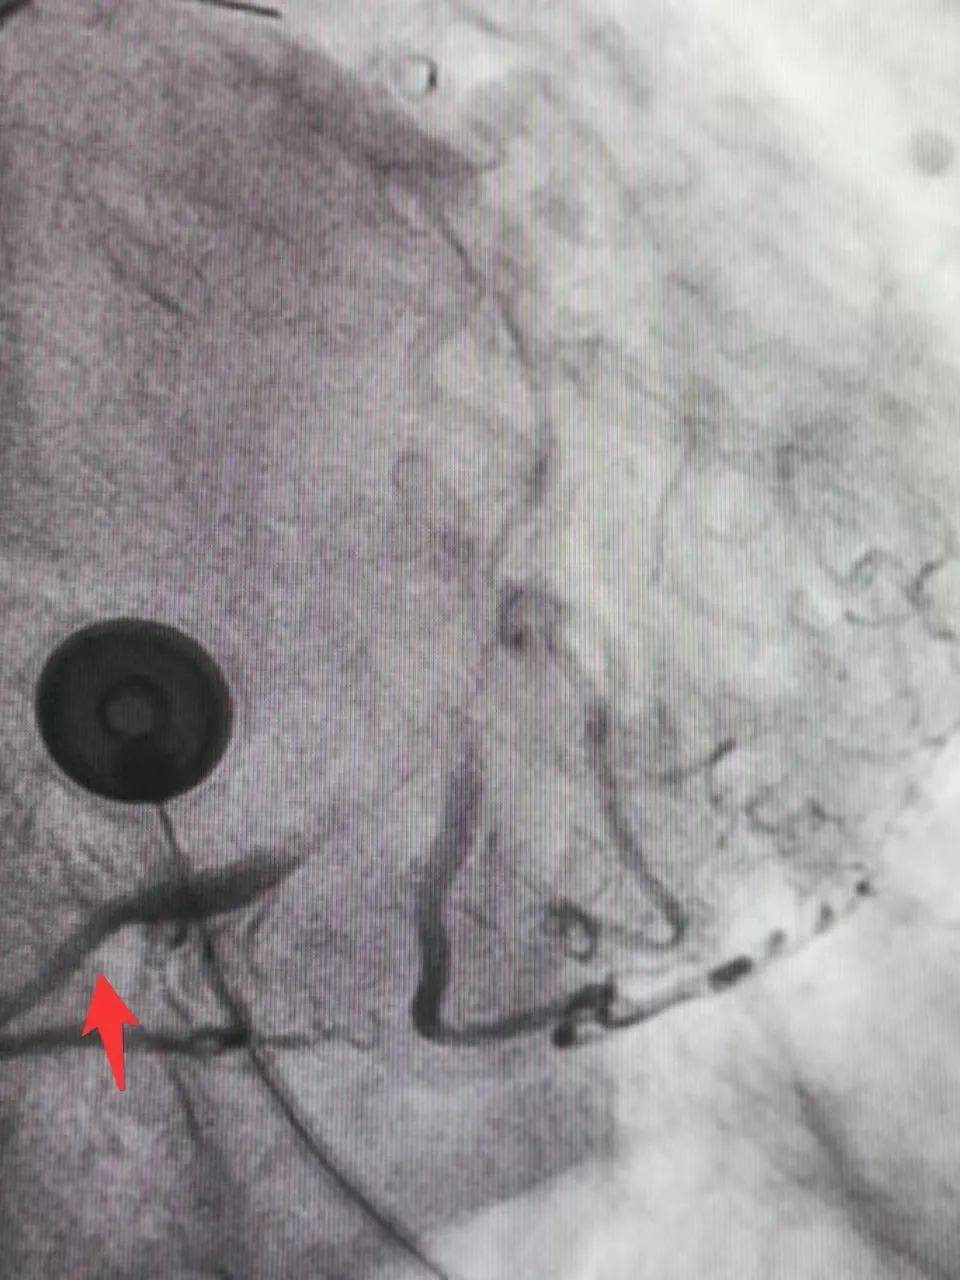

经家属同意,立即启动绿色通道,进行手术。最终,经过经皮冠状动脉介入微创手术(PCI), 畅通堵塞的血管,让血液流通至缺血的心肌。

▲治疗前,血管闭塞

▲治疗后,血管畅通